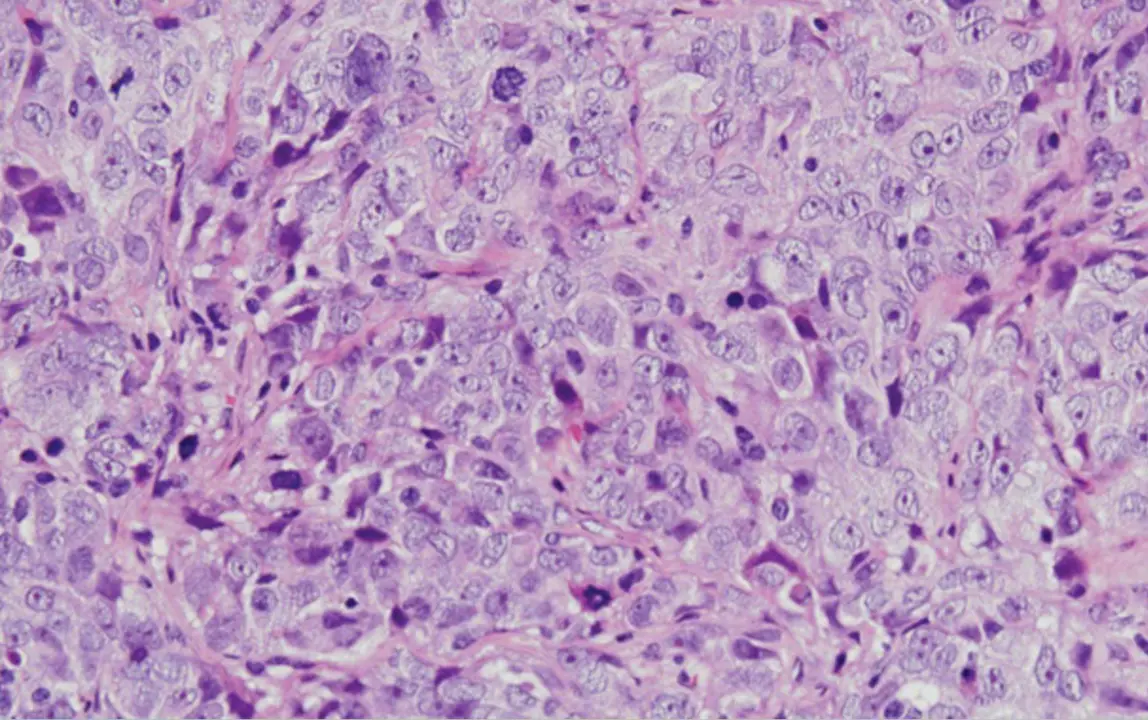

Cáncer de ovario seroso de alto grado - CSIC

El cáncer de ovario es uno de los cánceres ginecológicos más mortales en las mujeres. Cada año se diagnostican en todo el mundo unos 300.000 nuevos casos y se producen unas 200.000 muertes. La mayoría de los cánceres de ovario son de origen epitelial y, de ellos, más del 70 por ciento se catalogan como tumores de ovario de alto grado y suelen diagnosticarse en un estadio avanzado, dado que no presentan síntomas ni signos específicos en su fase inicial. Estas circunstancias le confieren un mal pronóstico y exigen el desarrollo de nuevas estrategias terapéuticas para combatir la evolución de la enfermedad.

Esto llevó a la identificación de una proteína, denominada WNK1, que se encontraba anormalmente activa en las líneas celulares analizadas. Este resultado impulsó el análisis del estado de activación de esta proteína en tumores de pacientes diagnosticadas con diferentes tipos de cáncer de ovario en el Hospital Universitario de Salamanca, revelando que la activación anormal de WNK1 afectaba drásticamente a la supervivencia de las pacientes.